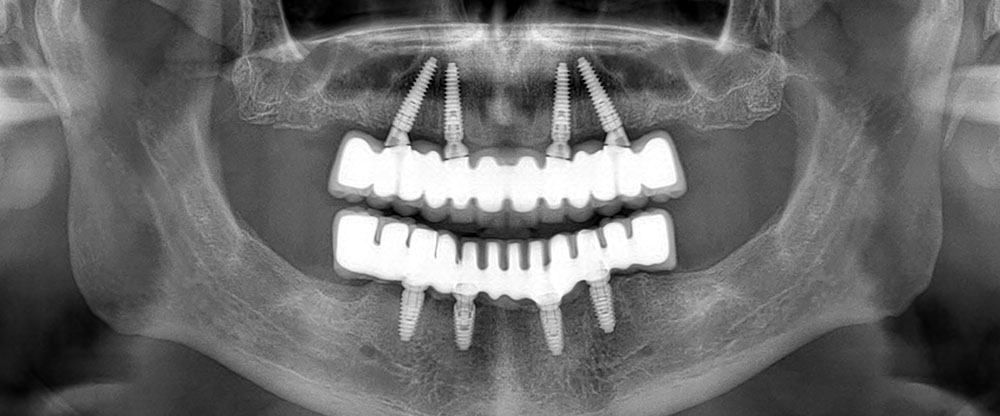

All-on-4: This system uses four implants per jaw. Two are placed straight in the front, and two are tilted at an angle in the back. This tilting allows us to anchor the implants in parts of the jaw that naturally have more bone.

All-on-6: This system uses six implants per jaw. These are typically distributed across the arch, providing additional points of support and creating a very rigid foundation for the new teeth.